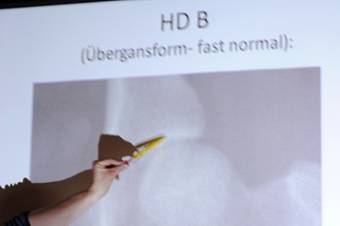

Teilgenommen haben fast 50 Mitglieder und Gäste. Ausführlich wurde beleuchtet, was HD ist, wie die HD-Untersuchung (Röntgen) durchgeführt wird, die Unterscheidung der einzelnen Stufen der HD (Bewertungsgrade), die Bedeutung der HD-Untersuchung und auch die Verbesserungsmöglichkeiten / Hilfen bei Befund. Herr Dr. Koch referierte gekonnt, souverän und unterhaltsam über die wichtigsten Aspekte und Maßnahmen. So gab er z.B. auch praktische Tipps über Futter bei Welpen und Junghunde, dass diese nicht zu lange sehr proteinreich gefüttert werden sollen und auch dass die Welpen nicht ständig auf glatten Böden ausrutschen sollten.